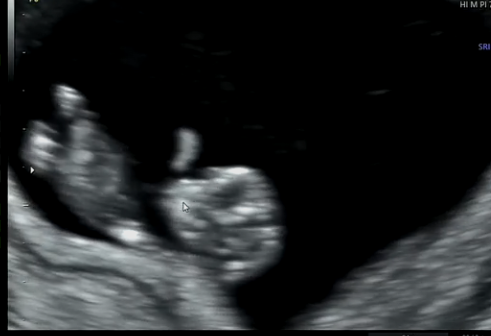

2024.11.26 - [● Momster's life] - ○ 8주 0일차. 팔 다리가 뿅뿅 자라고 있는 중✌🏼

○ 8주 0일차. 팔 다리가 뿅뿅 자라고 있는 중✌🏼

드디어 팔다리가 확실하게 자라있는 애기를 볼 수 있는건가요🎈

엄마 저 여깄어요~~~~ 하면서 보여주셨다.

ㅠㅠㅠㅠㅠㅠㅠㅠㅠㅠ팔다리도 튼튼하게 자랐고

심지어 움직이기까지한다..

움직이는거 처음보는데 진짜 엉엉울뻔..

너무 대견하게 꼬물꼬물 혼자서 팔을 휘휘 아주 자그맣게 움직이는데

마치 작은 고양이가 꾹꾹이 하는 것 같기도 하고..

가만히 있다가도 갑자기 딸국질 하듯 놀라기도 하고..

뭔가 처음으로 존재감을 확실하게 인지할 수있었다..

샘이 이리저리 머리사이즈 길이 등등 다 확인해주고

투명대도 아직 정상이고 봐주셨다.